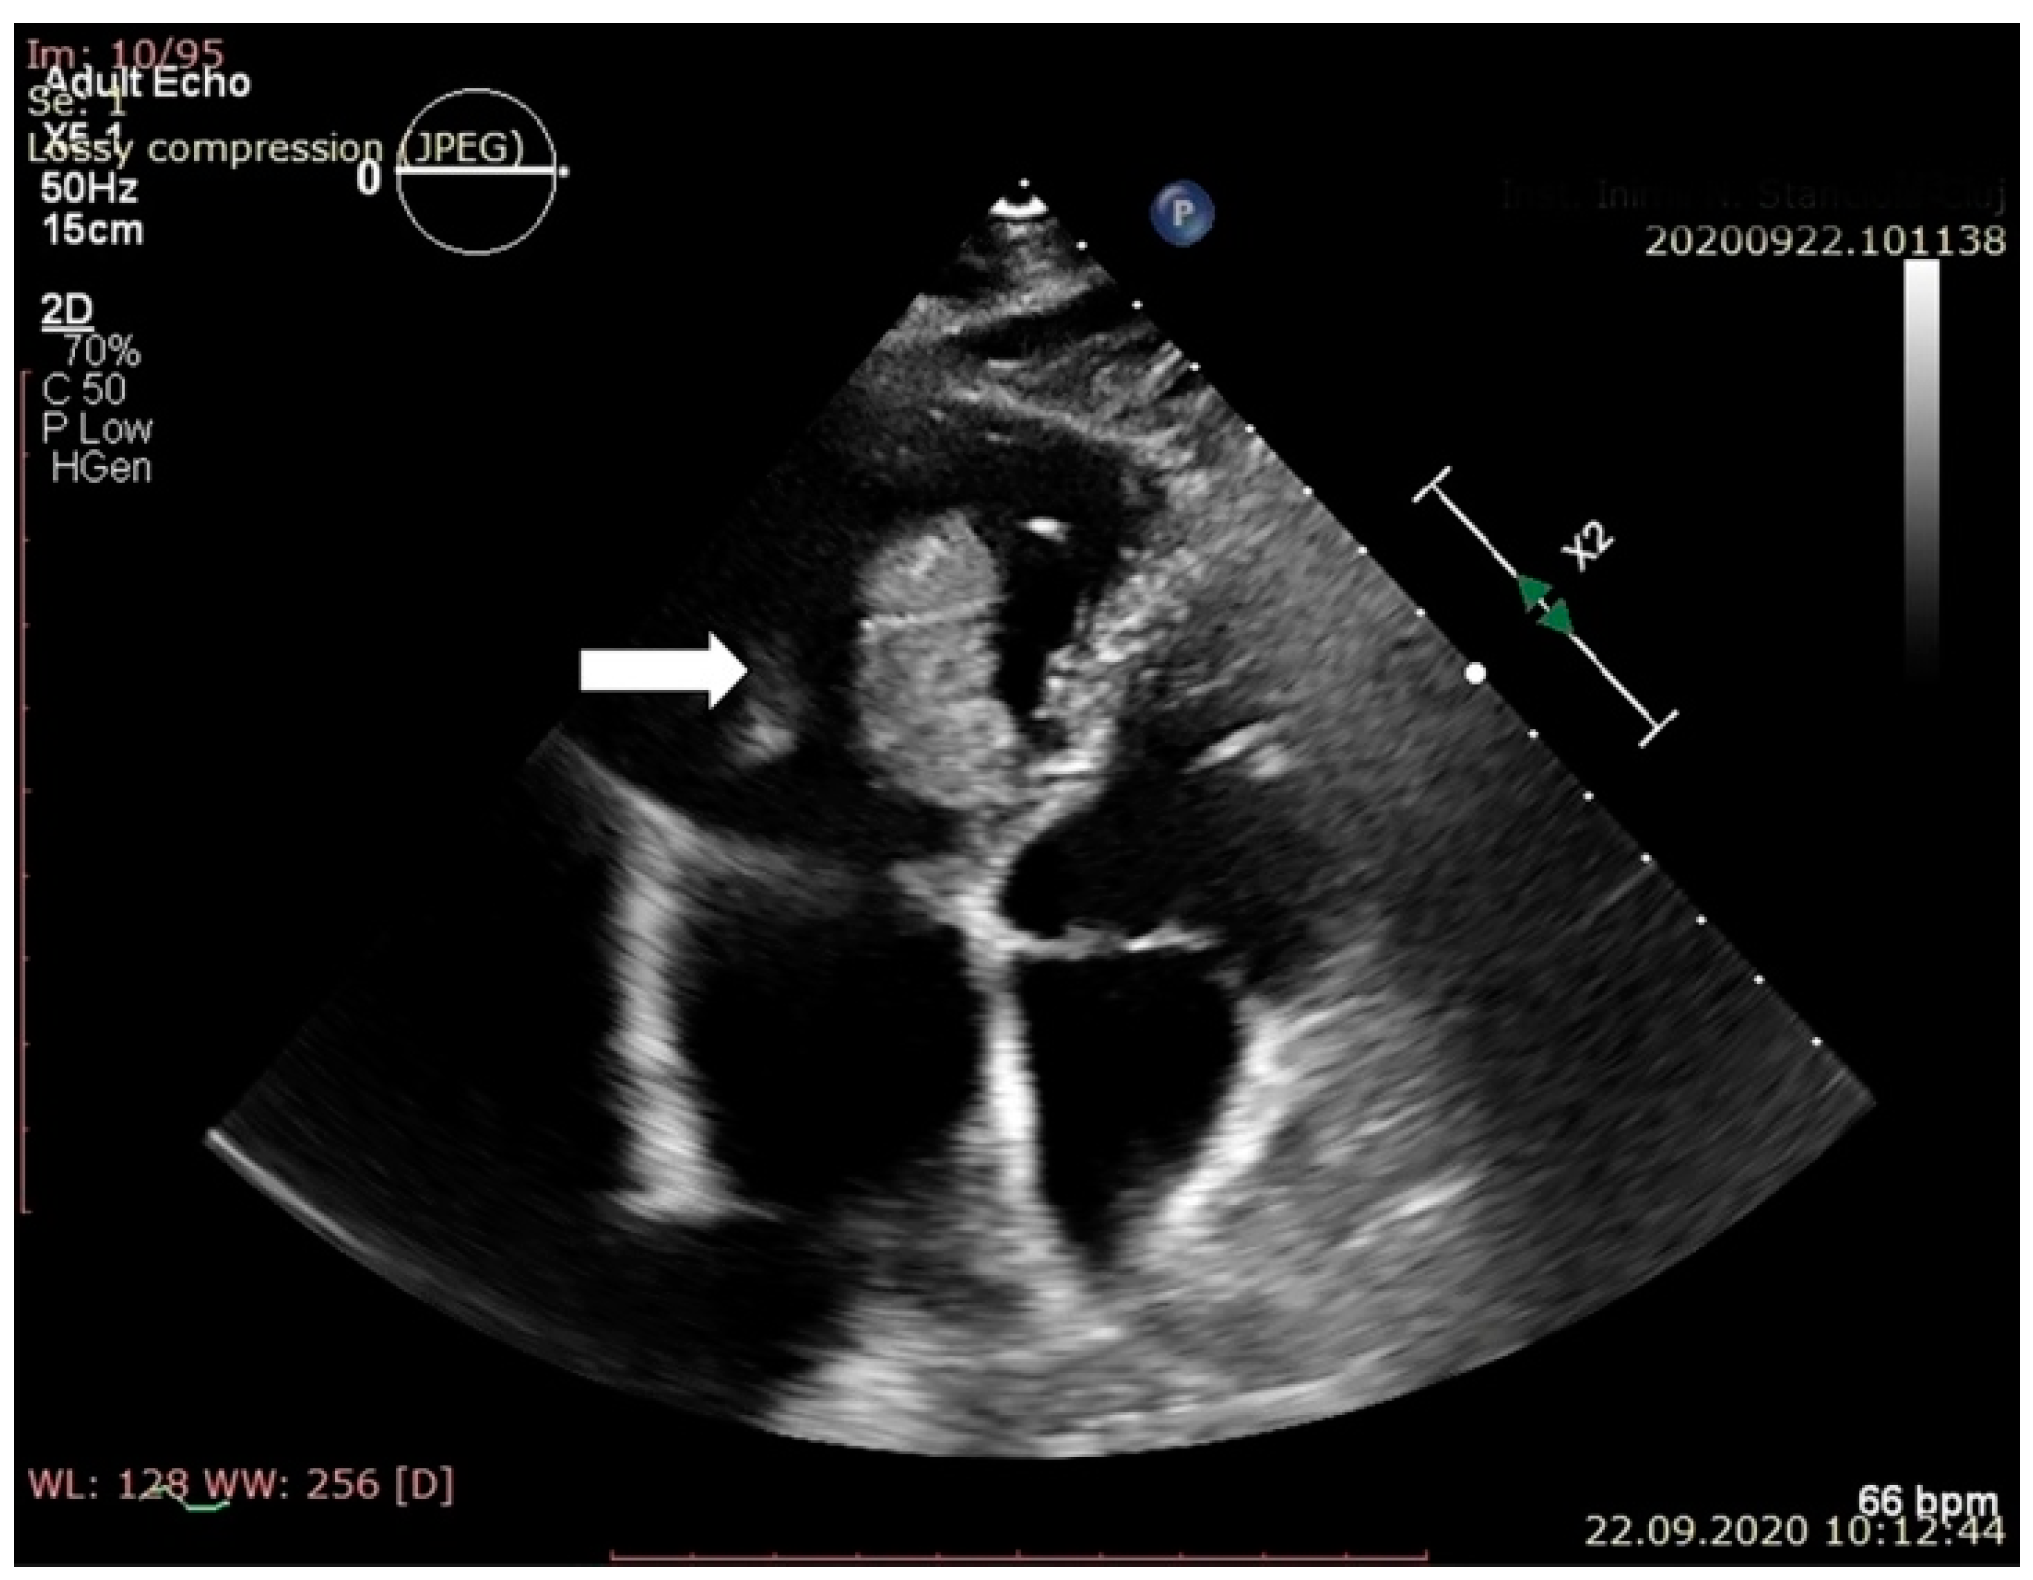

2. Case Report